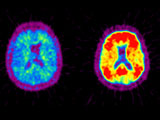

Maladie d’Alzheimer : va-t-on bientôt la prédire ?

Les progrès réalisés dans la détection précoce de la maladie d'Alzheimer laissent envisager la possibilité d'un dépistage des personnes à risque. Mais à quoi bon prédire la maladie si l'on ne sait toujours pas la soigner ? A l'occasion de la journée mondiale Alzheimer le 21 septembre 2008, le point sur cette délicate question.